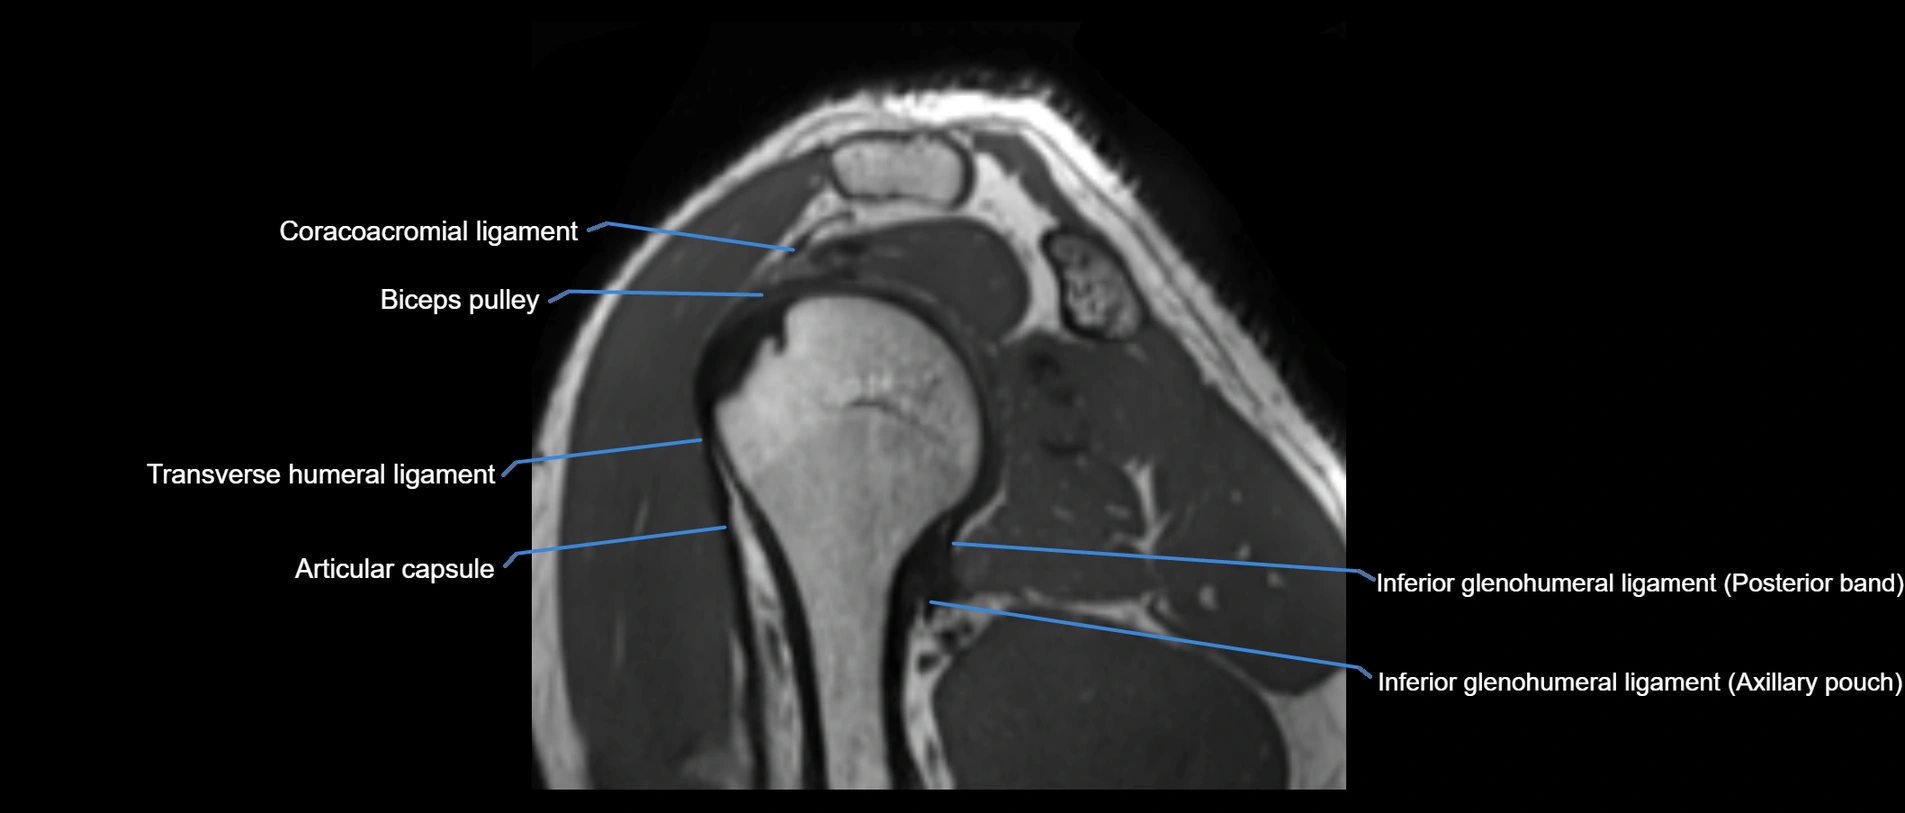

CT image

image

CT Appearance

Non-Contrast CT:

• Ligament: Not directly visualized due to small size and low density.

• Bony landmarks: Lateral clavicle and acromion clearly seen; cortical margins well defined.

• Pathology: Detects fractures, joint subluxation, osteophytes, and degenerative changes.

• Alignment assessment: Evaluates AC joint spacing and clavicular displacement.

Post-Contrast CT (standard):

• Ligament itself: Non-enhancing fibrous band.

• Inflamed capsule or soft tissue: May show enhancement.

• Useful for: Evaluating post-traumatic deformities, ossified ligaments, and chronic AC joint arthropathy.